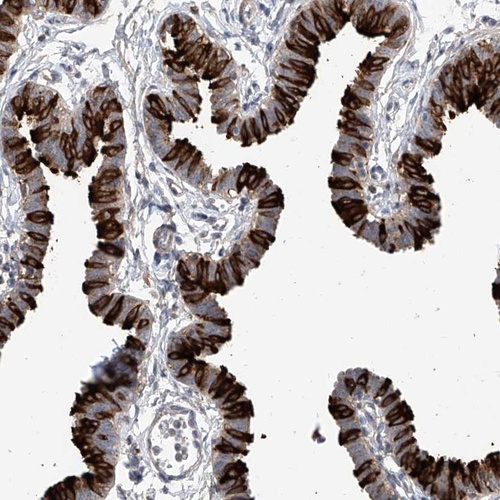

Immunohistochemistry analysis in human fallopian tube and liver tissues using Anti-RSPH4A antibody. Corresponding RSPH4A RNA-seq data are presented for the same tissues.